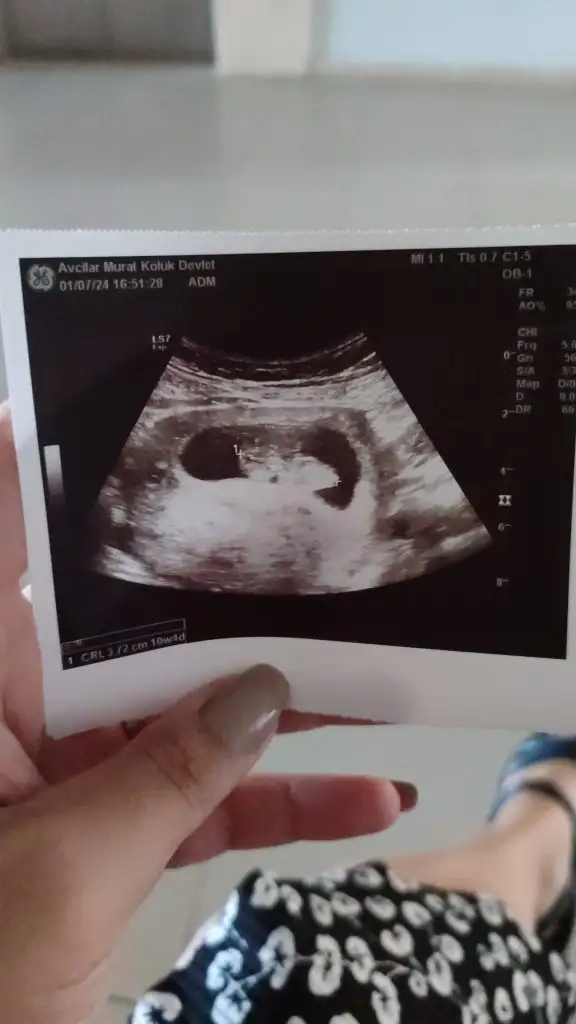

Bence kız Nub eğik açıBizede tahmin yapabilir misiniz acaba 10+4 üz![]()

Ben nubu göremedim doktor yan çekmemiş önden çekmiş ya onyüzden hiç yorumlayamadımBence kız Nub eğik açı![]()

Canım merhaba bende çok merak ediyorum sırf bu yüzden özele gidip ultrason aldım benımkıne de bakar mısınız rica etsem hepinizin yorumunu merak ediyorumKesinlikle kızzzz nub'u eğik